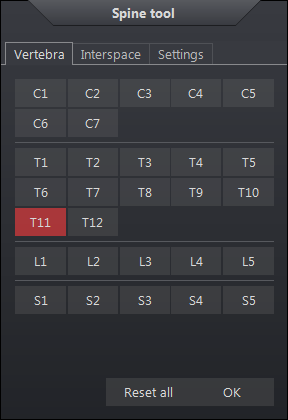

Spine Labeling

The spine labeling cursor will label disc vertebrae and disk interspaces. These predefined labels are displayed in their corresponding location on images in all orthogonal planes.

To insert a spine label:

- Select the Spine Labeling icon

- Left click the icon next to each vertebrae or interspace to place a level annotation

- Select the next vertebrae or interspace to place the next level

Right clicking on the screen will reveal a spine label control panel. This box allows the user to reset the labeling for the vertebrae and the interspace and choose new levels.

The settings tab contain these following options which are reset when the control panel is restarted:

| Spine Labeling Settings | Description |

|

Include L6 |

include L6 after L5 |

|

Reverse direction |

when enabled, labels progress in opposite direction |

|

Show Lines |

Display tether lines from the label to the focus point |

|

Hide Panel Automatically |

Hide the spine label control panel automatically after drawing the first spine label. |

|

Axial, Coronal, Sagittal |

Spine labels are displayed on all images in the relative plane. Applies at the time the image is annotated. |

|

Applied Plane |

Display the labels on the images in the same plane as the one used to annotate the spine. |

In order to place specified labels in the orthogonal images, the graphic must intersect the image within the defined distance from the focus point which will then appear in the intersecting plane. The spine labels appear in all orthogonal images automatically. If the frame of reference is not predefined, the images would have to be labeled individually. If the focus point falls outside the distance specified, no label appears.